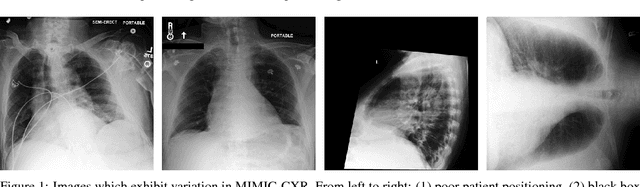

Abstract:Chest radiography is an extremely powerful imaging modality, allowing for a detailed inspection of a patient's thorax, but requiring specialized training for proper interpretation. With the advent of high performance general purpose computer vision algorithms, the accurate automated analysis of chest radiographs is becoming increasingly of interest to researchers. However, a key challenge in the development of these techniques is the lack of sufficient data. Here we describe MIMIC-CXR, a large dataset of 371,920 chest x-rays associated with 227,943 imaging studies sourced from the Beth Israel Deaconess Medical Center between 2011 - 2016. Each imaging study can pertain to one or more images, but most often are associated with two images: a frontal view and a lateral view. Images are provided with 14 labels derived from a natural language processing tool applied to the corresponding free-text radiology reports. All images have been de-identified to protect patient privacy. The dataset is made freely available to facilitate and encourage a wide range of research in medical computer vision.